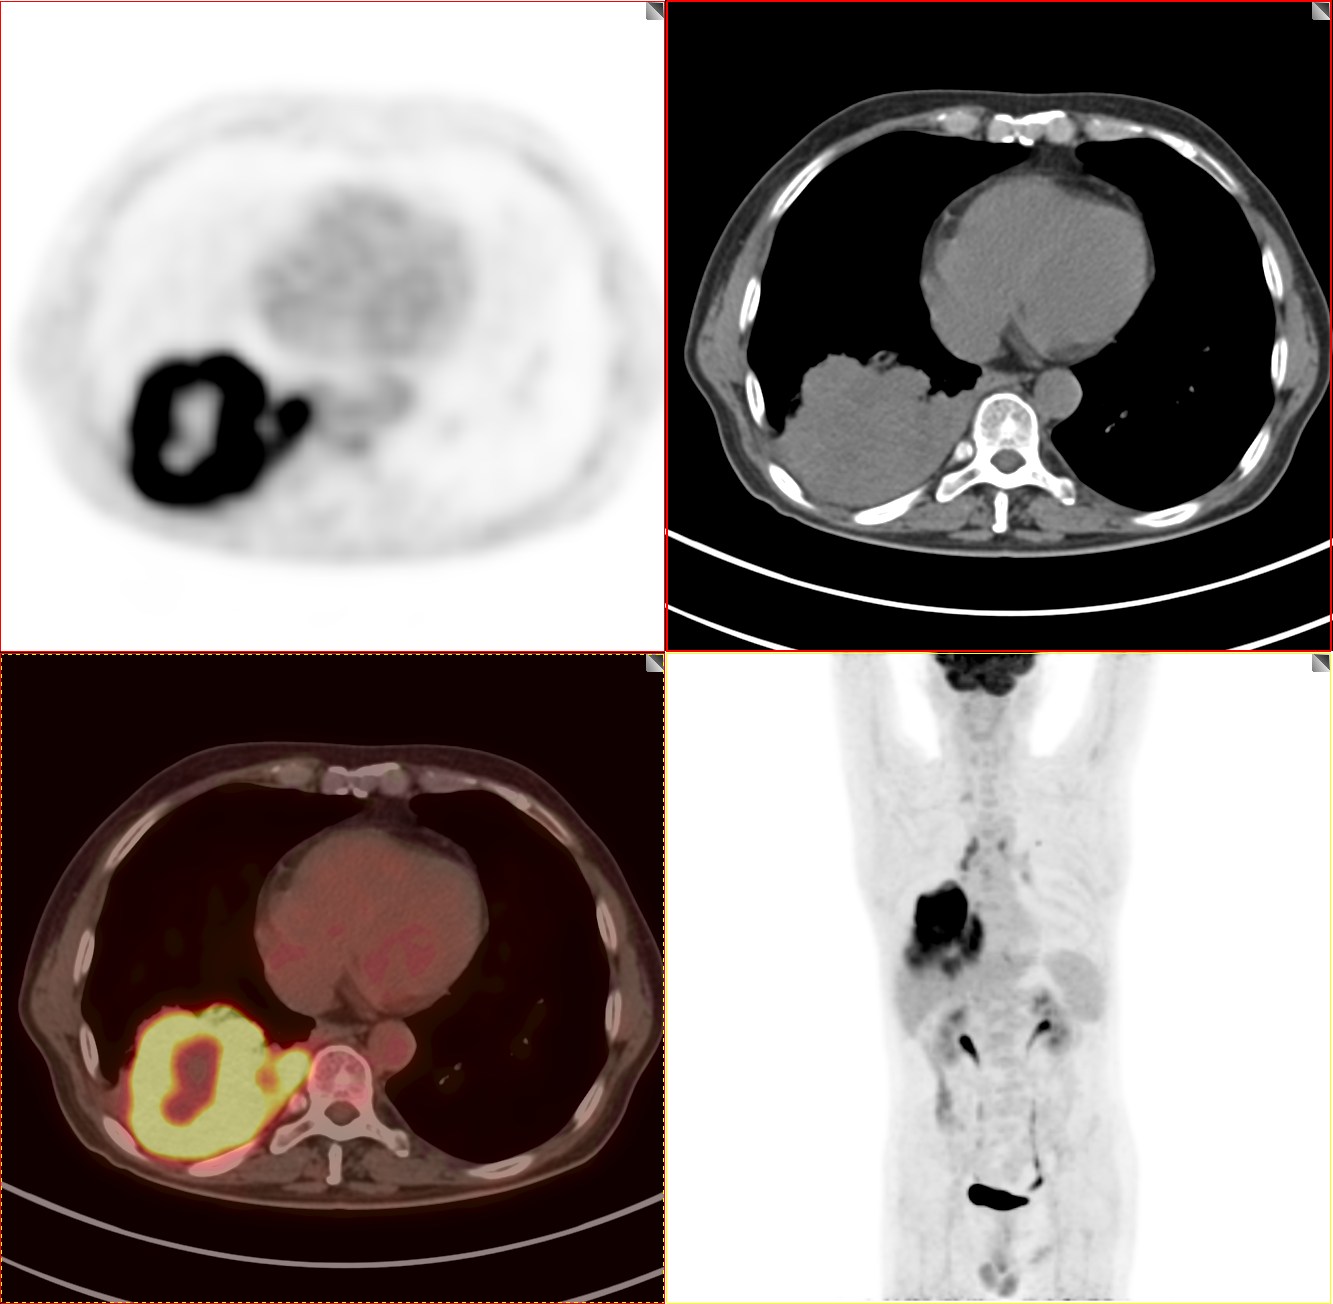

这个肿块CT诊断诊断不难,能明确是肺癌,但下一步处理必须进行肿瘤分期。一定要明确全身情况,进行肿瘤分期。通过第一次PET/CT检查的图像,我们做一个肿瘤分期,看看这个病变有没有转移。肺癌包括其他恶性肿瘤治疗,第一步就是进行肿瘤分期。

病灶FDG代谢明显增高

我们看着一团"火"一样的病灶就是这个肺癌,由于肿瘤生长速度快,血供跟不上,中心出现液化坏死区,中央出现一个“窟窿”。

病灶累及胸膜

胸腔少量积液

上面两张图提示病灶累及胸膜胸腔出现少量积液。非常幸运的是该患者没有出现明显的区域淋巴结转移及远处转移。由于病灶太大,相邻胸膜受到累及。依据NCCN、AJCC最新指南我们进行肿瘤分期。

T分期:T4

N分期:N0

M分期:M1a

综合分期:Ⅳa期